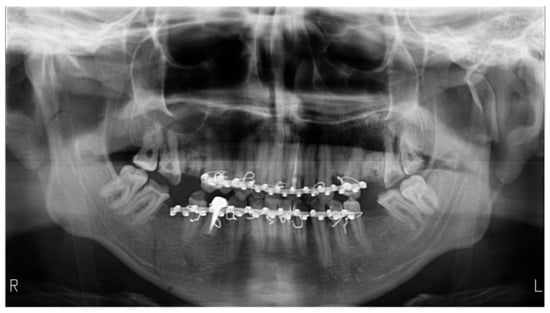

| Radiographs with bimaxillary immobilization errors | 23 | 76.66 | 62.16 | [59.07–88.21] * |